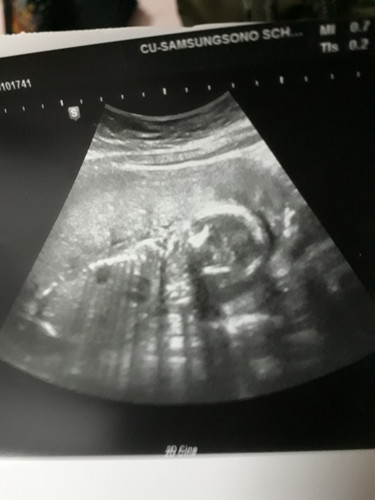

หมอบอกยังไม่ชัวร์นะ รูปซาวตอน5เดือน เดือนที่6-7หมอยังไม่ซาวให้เลยคะ รบกวนคนดูออกช่วยบอกหน่อยนะค่ะ

รูปนี้เหมืนด้านหลังของน้องเลยค่ะแม่ดูไม่ออก

รูปนี้ดูเพศไม่ได้จ๊ะ